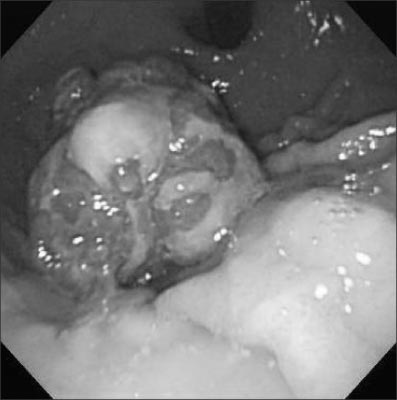

An ultrasonographic scan showed no remarkable abnormal findings. Upper gastrointestinal endoscopy revealed a 3 cm-sized polypoid mass with bleeding at the lesser curvature of the upper gastric body (

Fig. 1). At first, we planned to carry out an endoscopic polypectomy, but the polyp had such a large base that the polypectomy could not be performed. Therefore we chose to carry out an open laparotomy instead.

Fig. 1Endoscopic finding shows multi-lobulated polypoid mass with oozing at upper body of stomach.